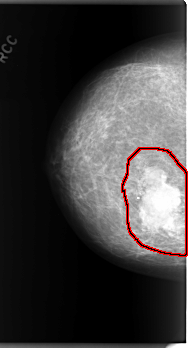

C_0066_1.RIGHT_CC

FILE: C_0066_1.RIGHT_CC.OVERLAY

TOTAL_ABNORMALITIES 1

ABNORMALITY 1

LESION_TYPE CALCIFICATION TYPE PLEOMORPHIC DISTRIBUTION CLUSTERED

LESION_TYPE MASS SHAPE LOBULATED MARGINS MICROLOBULATED

ASSESSMENT 5

SUBTLETY 5

PATHOLOGY MALIGNANT

TOTAL_OUTLINES 1

BOUNDARY